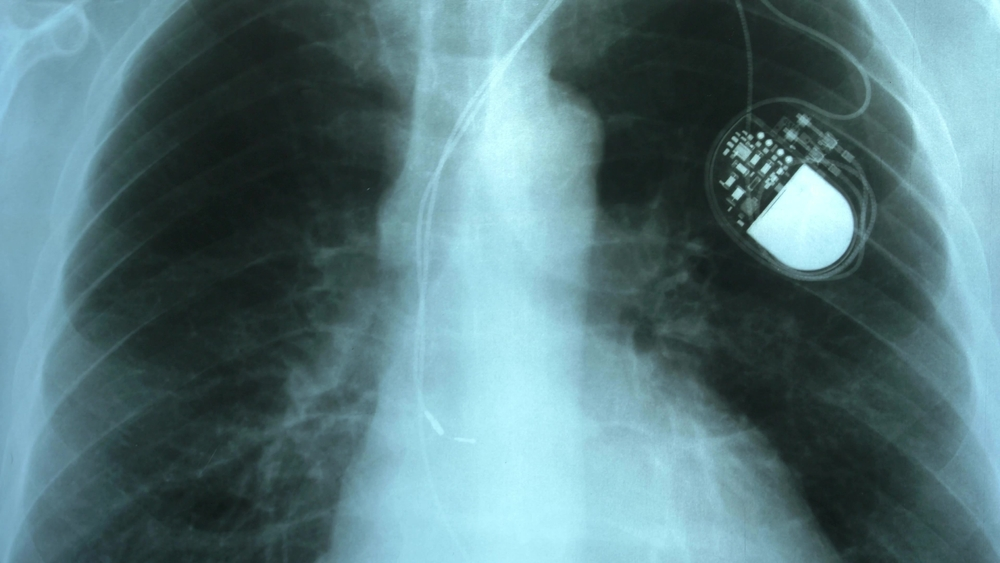

• A pacemaker is a small, battery-operated device that’s implanted in the chest to help regulate a person’s heartbeat. It sends electrical signals to the heart to ensure it beats at a steady, proper rate. Pacemakers are most commonly implanted when the heart’s natural pacemaker (known as the sinoatrial node) is not working properly.

• Pacemakers are about the size of a half-dollar or book of matches, however they can be a little larger or much smaller, depending on the type. The devices in question are the larger versions.

• Pacemakers work by sending small electrical pulses to the heart muscle, causing it to contract and pump blood. These electrical signals are similar to those your body would naturally produce to make a muscle contraction.

• Some pacemakers are literally on all the time to keep the heart’s rhythm at thcorrectht rate. People with these pacemakers are known as pacemaker-dependent. Other pacemakers only turn on when they detect a problem with the heartbeat and need to intervene.